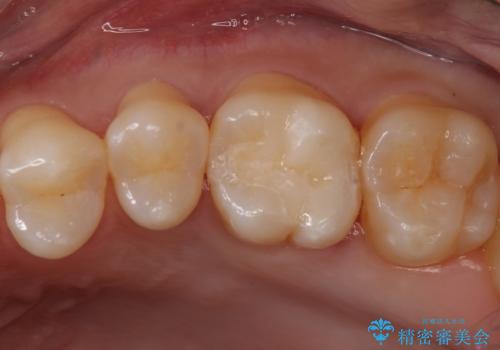

同じような樹脂の詰め物での治療ではまた虫歯ができることが予想されるため、今回はセラミックインレーで修復することとなりました。

以前樹脂を詰めた結果再び虫歯ができてしまっていることから、同じ治療は同じ結果になる可能性があるため今回はアプローチを変えてセラミックインレーで修復処置をしていくこととなりました。

虫歯の取り残しや、不適合な詰め物は再治療のリスクとなります。

適合の良い修復物を入れることは今後の虫歯リスクを抑えることに繋がります。